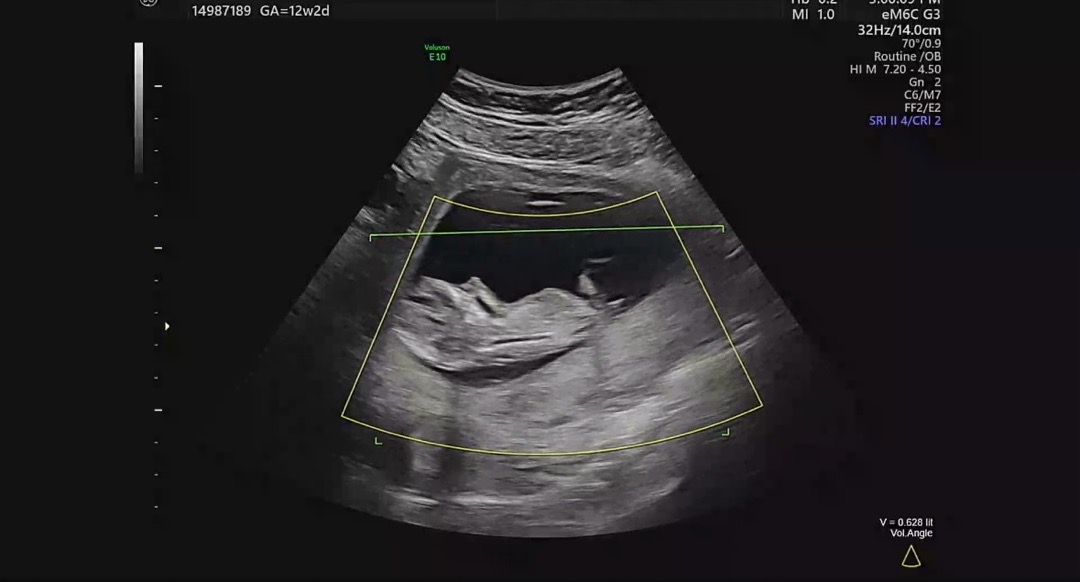

12주2일 각도법 궁금합니다!!

사진이 흐릿하긴한데 알수있을까요?? 다른분들 초음파 사진 봐도봐도 전 모르겠네요;;;

요건 많이 흐릿한듯해요 초음파영상보고 잘나온부분 캡쳐도가능해요~